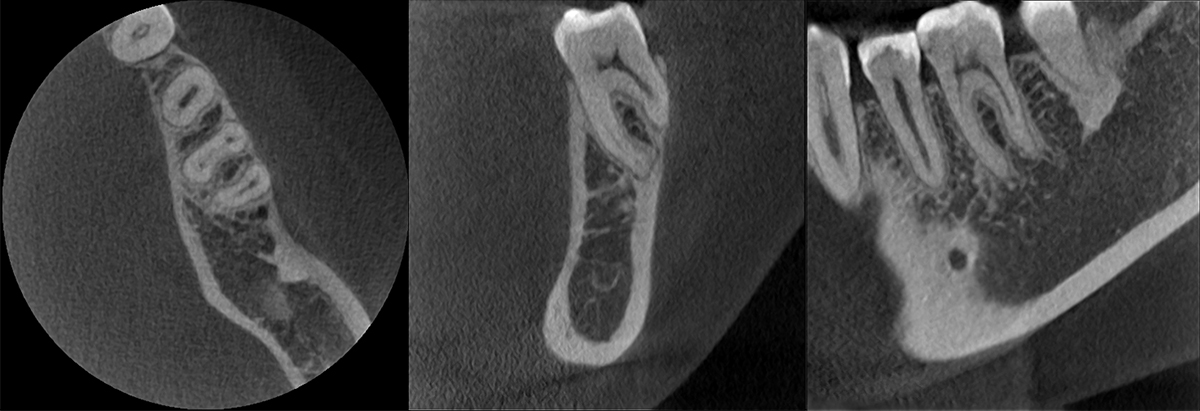

Excelentes imágenes de TC

El modo de alta definición, HD75µm, puede afrontar diagnósticos de conductos radiculares difíciles.

Patrón de conducto radicular